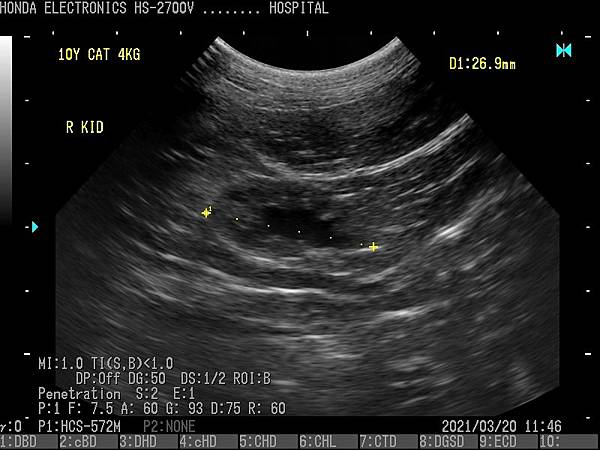

- 通過H-res獲得清晰豐富的單色圖像

HONDA獨創的圖像增強技術 H-res(我們的分辨率技術)

多年來超聲波技術的發展,結晶為“ H-res”圖像增強技術。

可以通過針對每種應用和探頭調整“ H-res”參數來獲得最佳圖像。

* 分辨率可在較淺的區域可視化精細的組織結構。* 穿透力可以在更深的器官中顯現出良好的分辨率。* 邊界可視化骨骼以進行觀察。* 清晰度降低了血管中的噪音。* 溫和會降低圖像增強效果。* OFF具有直接的超聲圖像。